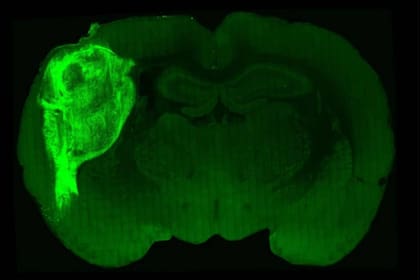

Para que los organoides cerebrales tuvieran esta estimulación y apoyo de nutrientes, se cultivaron estas estructuras a partir de células madre humanas y luego fueron inyectadas en los cerebros de crías de rata con pocos días de vida, con la expectativa de que las células de origen humano se desarrollaron a la par de las de las propias ratas.

El equipo de científicos de Stanford, encabezado por el neurocientífico Sergiu Pasca, colocó estos organoides en una región del cerebro de los roedores denominada corteza cerebral somatosensorial, que recibe las señales de los bigotes y otros órganos sensoriales de las ratas y luego las transmite a otras regiones cerebrales que interpretan estas señales, informó la agencia Europa Press.